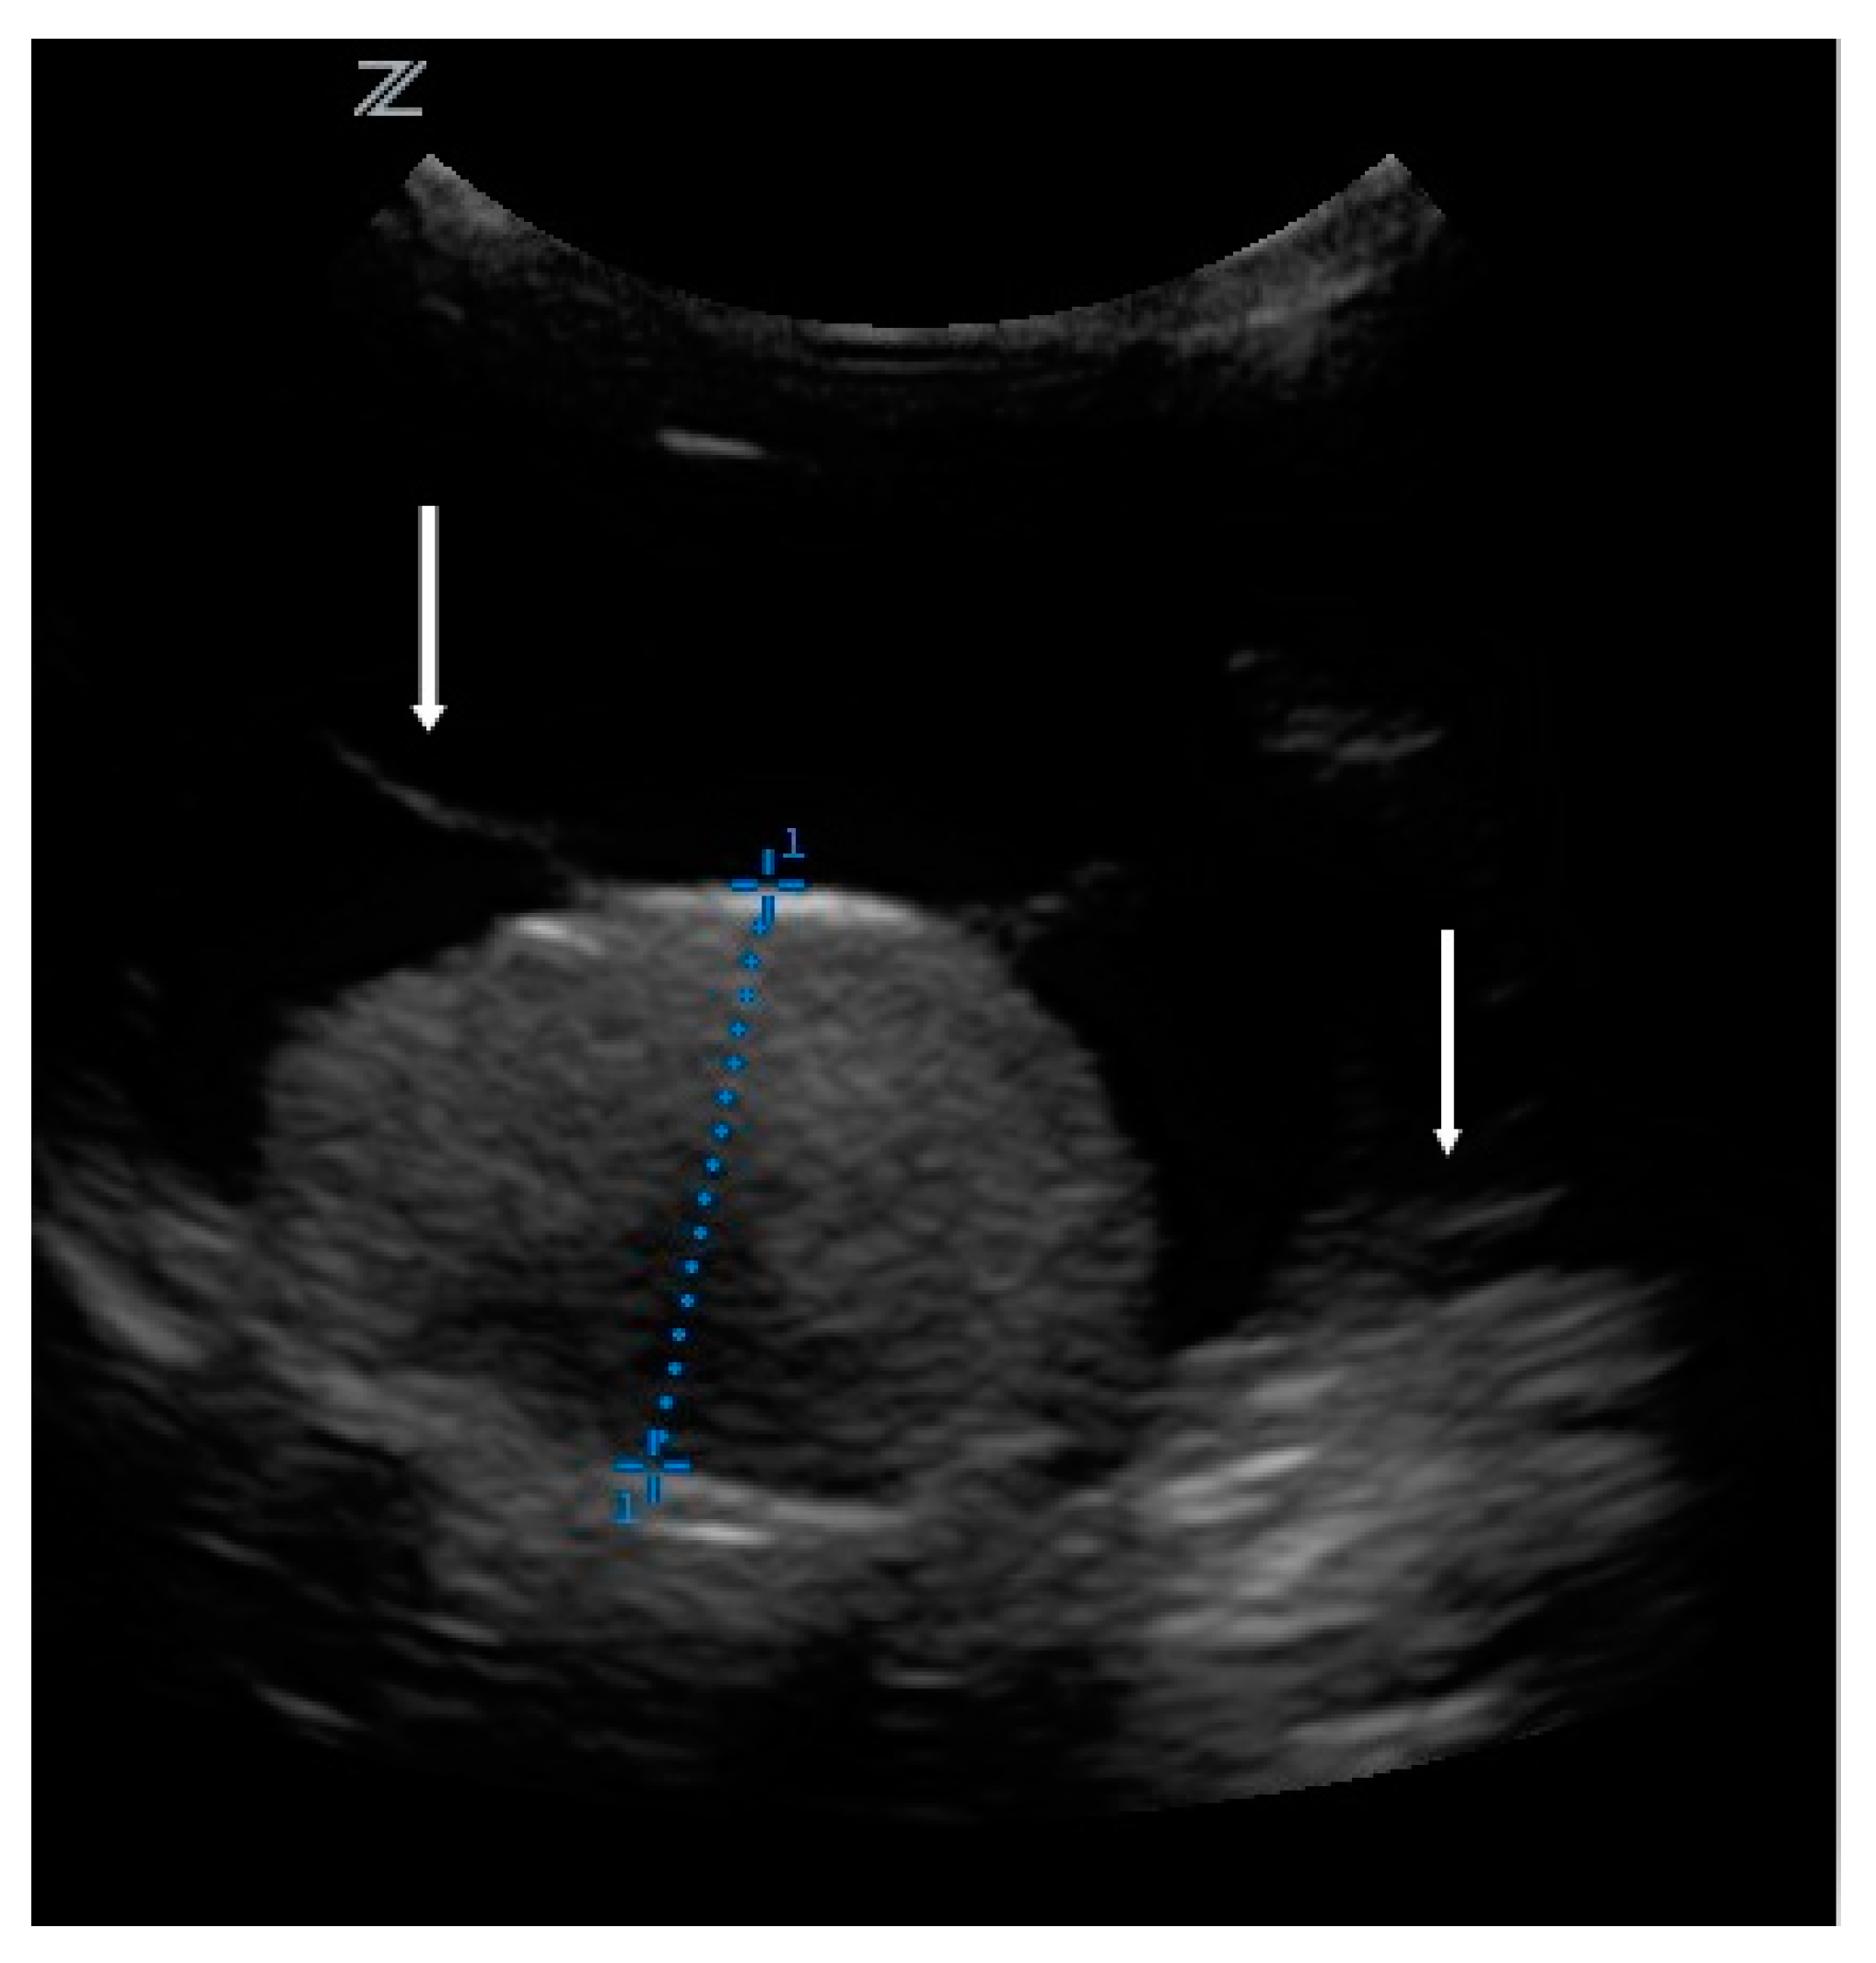

The owners brought the dog in for regular check-ups every week. Although blood tests did not uncover the cause of the retinal detachment, the therapy was continued due to the clinical improvement. The condition and behavior of the dog were normal, and he did not show pain. For the next 2 months, the nasal bullous protrusion disappeared and both pupils responded to light. However, after 2 months of treatment, the protrusion of the left retina recurred, and the left pupil reaction disappeared again. This prompted further investigations. Ultrasonography (z.one ultra, Zonare medical systems GmbH, Erlangen, Germany, C 10-3 transducer, 9 MHz) of the bulbus revealed a tumor. There was a 1.5 × 0.96 cm homogeneous moderate echogenic mass on the posterior fundus. The retina was floating in the vitreous body (Figure 2). Antibiosis and systemic cortisone treatment were terminated, but local cortisone treatment continued. Enucleation and histopathological examination were recommended. The owners did not agree due to the clinical improvement. Instead, they were willing to come in for ophthalmologic and sonographic check-ups every 4 weeks for the next 3 months, and then from every 2 to 3 months.

Figure 2. Ultrasonography of the bulbus. Diameter measured: 0.96 cm. Arrows: retina floating in the vitreous body.